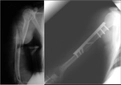

Bu belirtiler acil müdahale gerektiren durumlar arasında yer alır ve dikkatle değerlendirilmelidir. Tanı YöntemleriKalça kırığını teşhis etmek için çeşitli tanı yöntemleri kullanılmaktadır. Bunlar arasında:

Bu yöntemler, kalça kırığının tam yerini ve türünü belirlemek için kritik öneme sahiptir. Tedavi YöntemleriKalça kırığının tedavisi, kırığın tipi, hastanın yaşı ve genel sağlık durumu gibi faktörlere bağlı olarak değişiklik gösterir. Genel olarak kullanılan tedavi yöntemleri şunlardır: